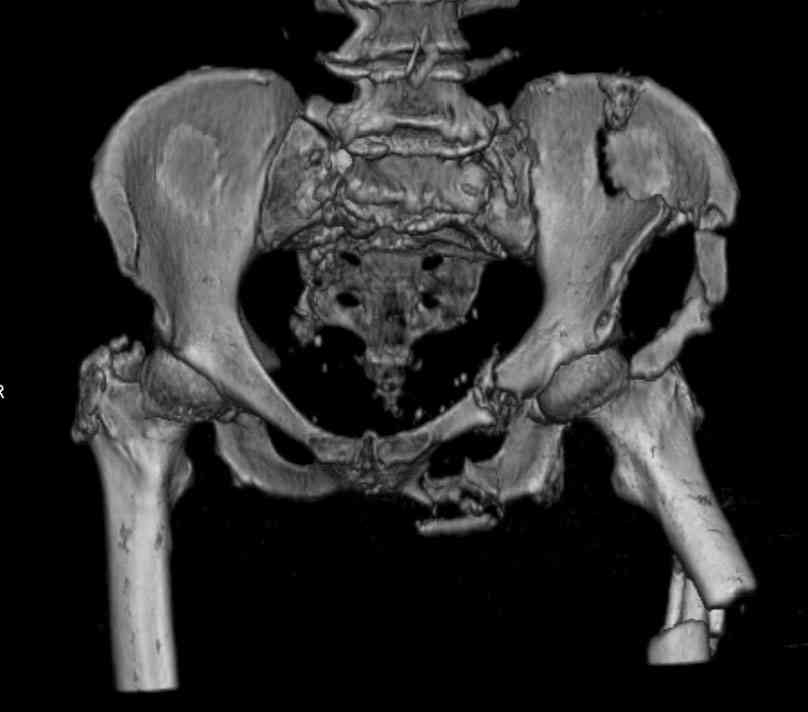

Здравствуйте уважаемые коллеги! Поступила пациентка, 61г, через 1 месяц после травмы, с двусторонним ротационно-нестабильным повреждением тазового кольца: перелом боковых масс крестца с обеих сторон, переломы лонной и седалищной костей слева, отрывные переломы передних остей левой подвздошной кости, сегментарный перелом левой подвздошной кости. Кроме того у пациентки имеется сегментарный перелом левого бедра. Перелом бедра не вызывает вопросов - планируем блокируемый остеосинтез стержнем, а вот при обсуждении тактики лечения переломов костей таза возник вопрос о необходимости синтеза остей подвздошной кости, учитывая сроки с момента травмы и наличие остеопороза могут возникнуть технические сложности. Если у кого-нибудь собственный опыт или ссылки на литературу об отдаленных результатах при не восстановлении сгибательного аппарата бедра?

Уважаемые коллеги, в продолжение обсуждения перелома костей таза с отрывами остей досылаю R-снимки (КТ и КТ с 3d реконструкцией)